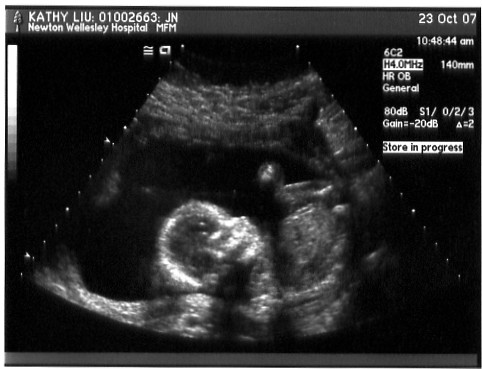

The doctor used the ultrasound wand to push down and get her to move into different positions so that all the required measurements could be taken. This shot is mostly just her head and upper torso - and perhaps a hand floating around?